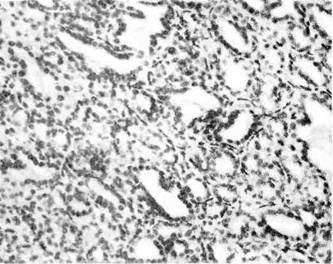

Н е и н ф и л ь т р и р у ю щ и й

про токовый рак (п р о т о к о-

вый «рак на мест е») существу-

ет в двух разновидностях — сосочко-

вый и угревидный рак. С о с о ч к о-

в ы й рак, растет, заполняя собой

просвет расширенных протоков, и не

выходит за их,пределы. Угревид-

ный рак возникает мультицент-

Рис. 146. Дольковый рак молочной железы.

Рис. 147. Прогоковый рак молотой железы.

Рис. 148. Пунктат из раковой опухоли

молочной железы.

рично, но обычно ограничивается одним сегментом железы. Внутрипрото-

ковые разрастания анаплазированного эпителия могут быть солидными,

железистыми, псевдососочковыми (рис. 147, 148). Выполняя просвет протока,

они подвергаются некрозу, что составляет главную особенность этой формы

рака: на разрезе опухоли некротические, иногда обызвествленные массы

выдавливаются из расширенных протоков в виде' белесоватых крошащихся

пробок. С течением времени внутрипротоковый рак, как и дольковый,

переходит в инвазивную форму.